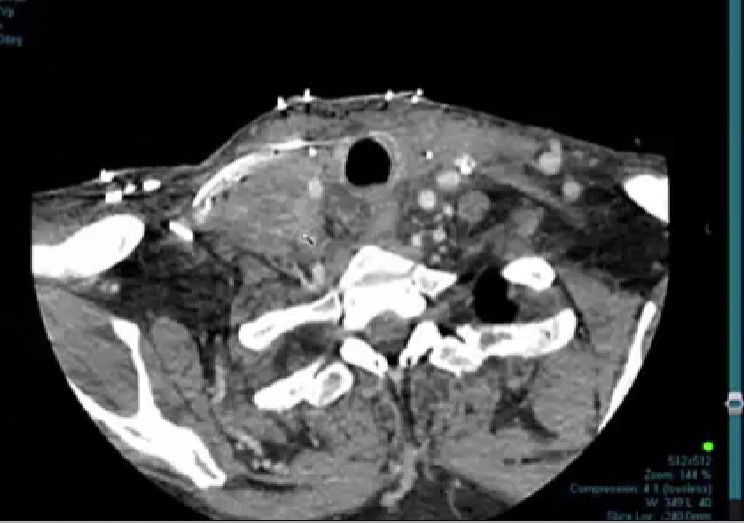

02/24/2025 - Dr. David Sher - Radiation Oncology - Head and Neck

advanced skin cancer, paranasal sinus cancer, infratemporal fossa